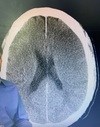

Perfectly

31 anos, cefaleia intensa há 3 dias com piora hoje, uso de ACO. Qual diagnóstico?

Trombose de seio cavernoso (TVC) com infarto do parênquima adjacente Área hipoatenuante cortico subcortical parietal à direita